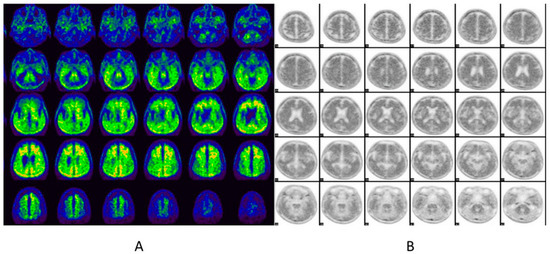

6.2. Brain Amyloid PET

6.2.1. Imaging Data Display [39]

- Gray scale: 18F-florbetaben

- Color (Rainbow): 11C-PiB, 18F-flutemetamol and 18F-NAV4694

- Reverse gray scale: 18F-florbetapir

- Maximum intensity of the display scale

- 18F-florbetapir: the brightest region of overall brain uptake

- 18F-florbetaben: the white matter maximum

- 18F-flutemetamol: setting the scale intensity in the pons region to 90%

6.2.2. Image Interpretation for Brain Amyloid PET

Visual Analysis [39,66,67,68]

Negative Scan

Positive Scan